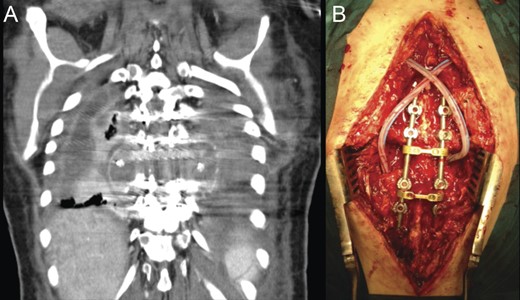

Concurrently, a newly resurged septated empyema had developed in the paravertebral space, which demanded for a combined anterior and posterior approach, for complete drainage (Fig. 7). Twelve days later, an additional posterior open drainage was necessary to address a subcutaneous abscess. Samples collected intraoperatively from this last operation isolated methicillin-resistant Staphylococcus aureus and Pseudomonas aeruginosa as pathogens.

(A) CT scan coronal reconstruction showing recurrence of paravertebral empyema. (B) Intraoperative image following posterior debridement.